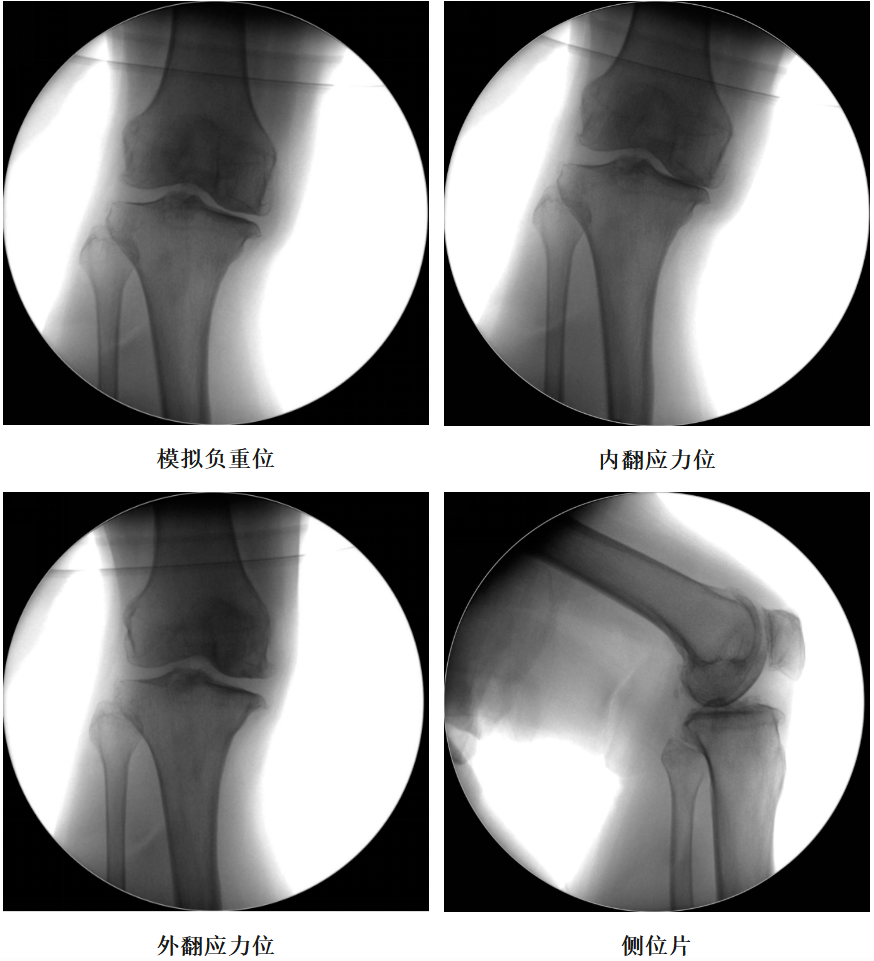

体格检查:右膝内翻畸形,约8°,无屈曲畸形。屈曲20°外翻应力下内翻畸形可纠正,屈曲90°可自行纠正。内侧关节间隙处压痛阳性。活动度:0°~115°。

X-Ray:右膝内侧间隙明显狭窄,站立位内侧间隙消失,外侧间隙正常,膝关节稳定。

诊断:右膝关节内侧间室OA。

术前透视片